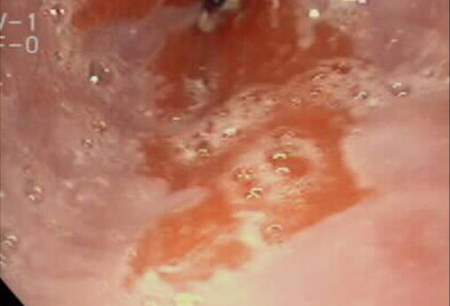

- upper GI endoscopy with biopsy

- chromoendoscopy